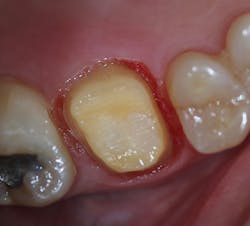

A final impression was made using a base VPS impression material (V-Posil Putty Fast, Voco; figure 11) followed by a light-body VPS impression material wash (V-Posil Light Fast, Voco; figure 12). A provisional crown was made using a cold-cure composite provisional material (Structur 3, Voco; figures 13 and 14) andcemented. The patient was dismissed. Upon return three weeks later, the provisional was removed and the definitive laboratory-fabricated zirconia crown was delivered.

Figure 13: Making of provisional crown

Figure 14: Provisional crown